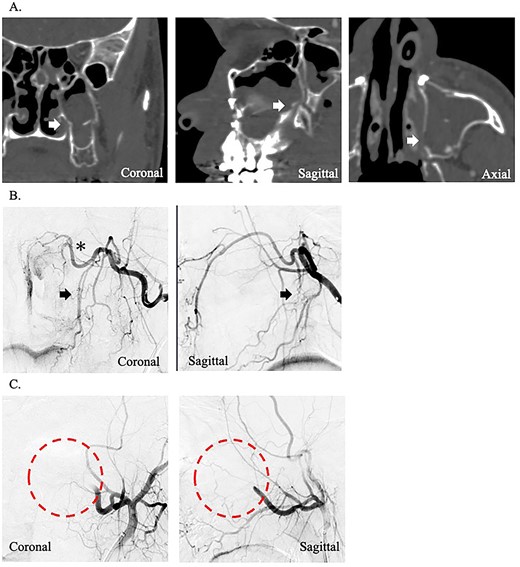

A 49-year-old woman with severe hemorrhage after Le Fort I maxillary osteotomy and sagittal split ramus osteotomy was transferred to our hospital. She underwent surgery for a jaw deformity 7 days earlier by the dentist at another hospital, and postoperative Day 5, severe epistaxis from the left nasal cavity occurred. At the previous hospital, the patient was treated for epistaxis by nasal tampons; however, the hemorrhage could not be completely stopped. After transport, an endoscope was used to search for the bleeding point from the left nasal cavity. The source of hemorrhage was identified near the natural ostium of the maxillary sinus. This massive was impossible to control under endoscopy; therefore, temporary hemostasis was used with nasal packing. Contrast-enhanced computed tomography of the paranasal area revealed that the maxilla and the pterygoid fragment were cut and separated. A cut of the bone was also found around the descending palatine artery, and blood was found within the maxillary sinus (Fig. 1A). The preoperative hemoglobin concentration was 12.6 g/dL, and the hematocrit was 38.0%. After transport, hemoglobin concentration slightly decreased to 11.2 g/dL and hematocrit to 34.6%. Since the bleeding point could not be identified by endoscopy and the hemorrhage continued, an angiographic embolization by a radiologist was selected as the hemostatic method. The angiography showed a pseudoaneurysm of the left descending palatine artery, on which embolization was performed by endovascular coils and gelatin sponges (Fig. 1B and C). Although hemostasis was achieved adequately after angiographic embolization, the hemoglobin concentration and hematocrit were further decreased to 9.8 g/dL and 30.0%, respectively.

(A) Postoperative coronal, sagittal, and axial computed tomography images, which show the separated bone parts of the left maxilla (arrow). (B) Coronal and sagittal selective angiographic images from the left internal maxillary artery. The arrow indicated a pseudoaneurysm of the left descending palatine artery. The asterisk indicated the left sphenopalatine artery. (C) After embolization and coronal and sagittal selective angiographic images. The Triangular arrow indicated the endovascular coils, and the circle indicated the disappearance of the vascular flow area.